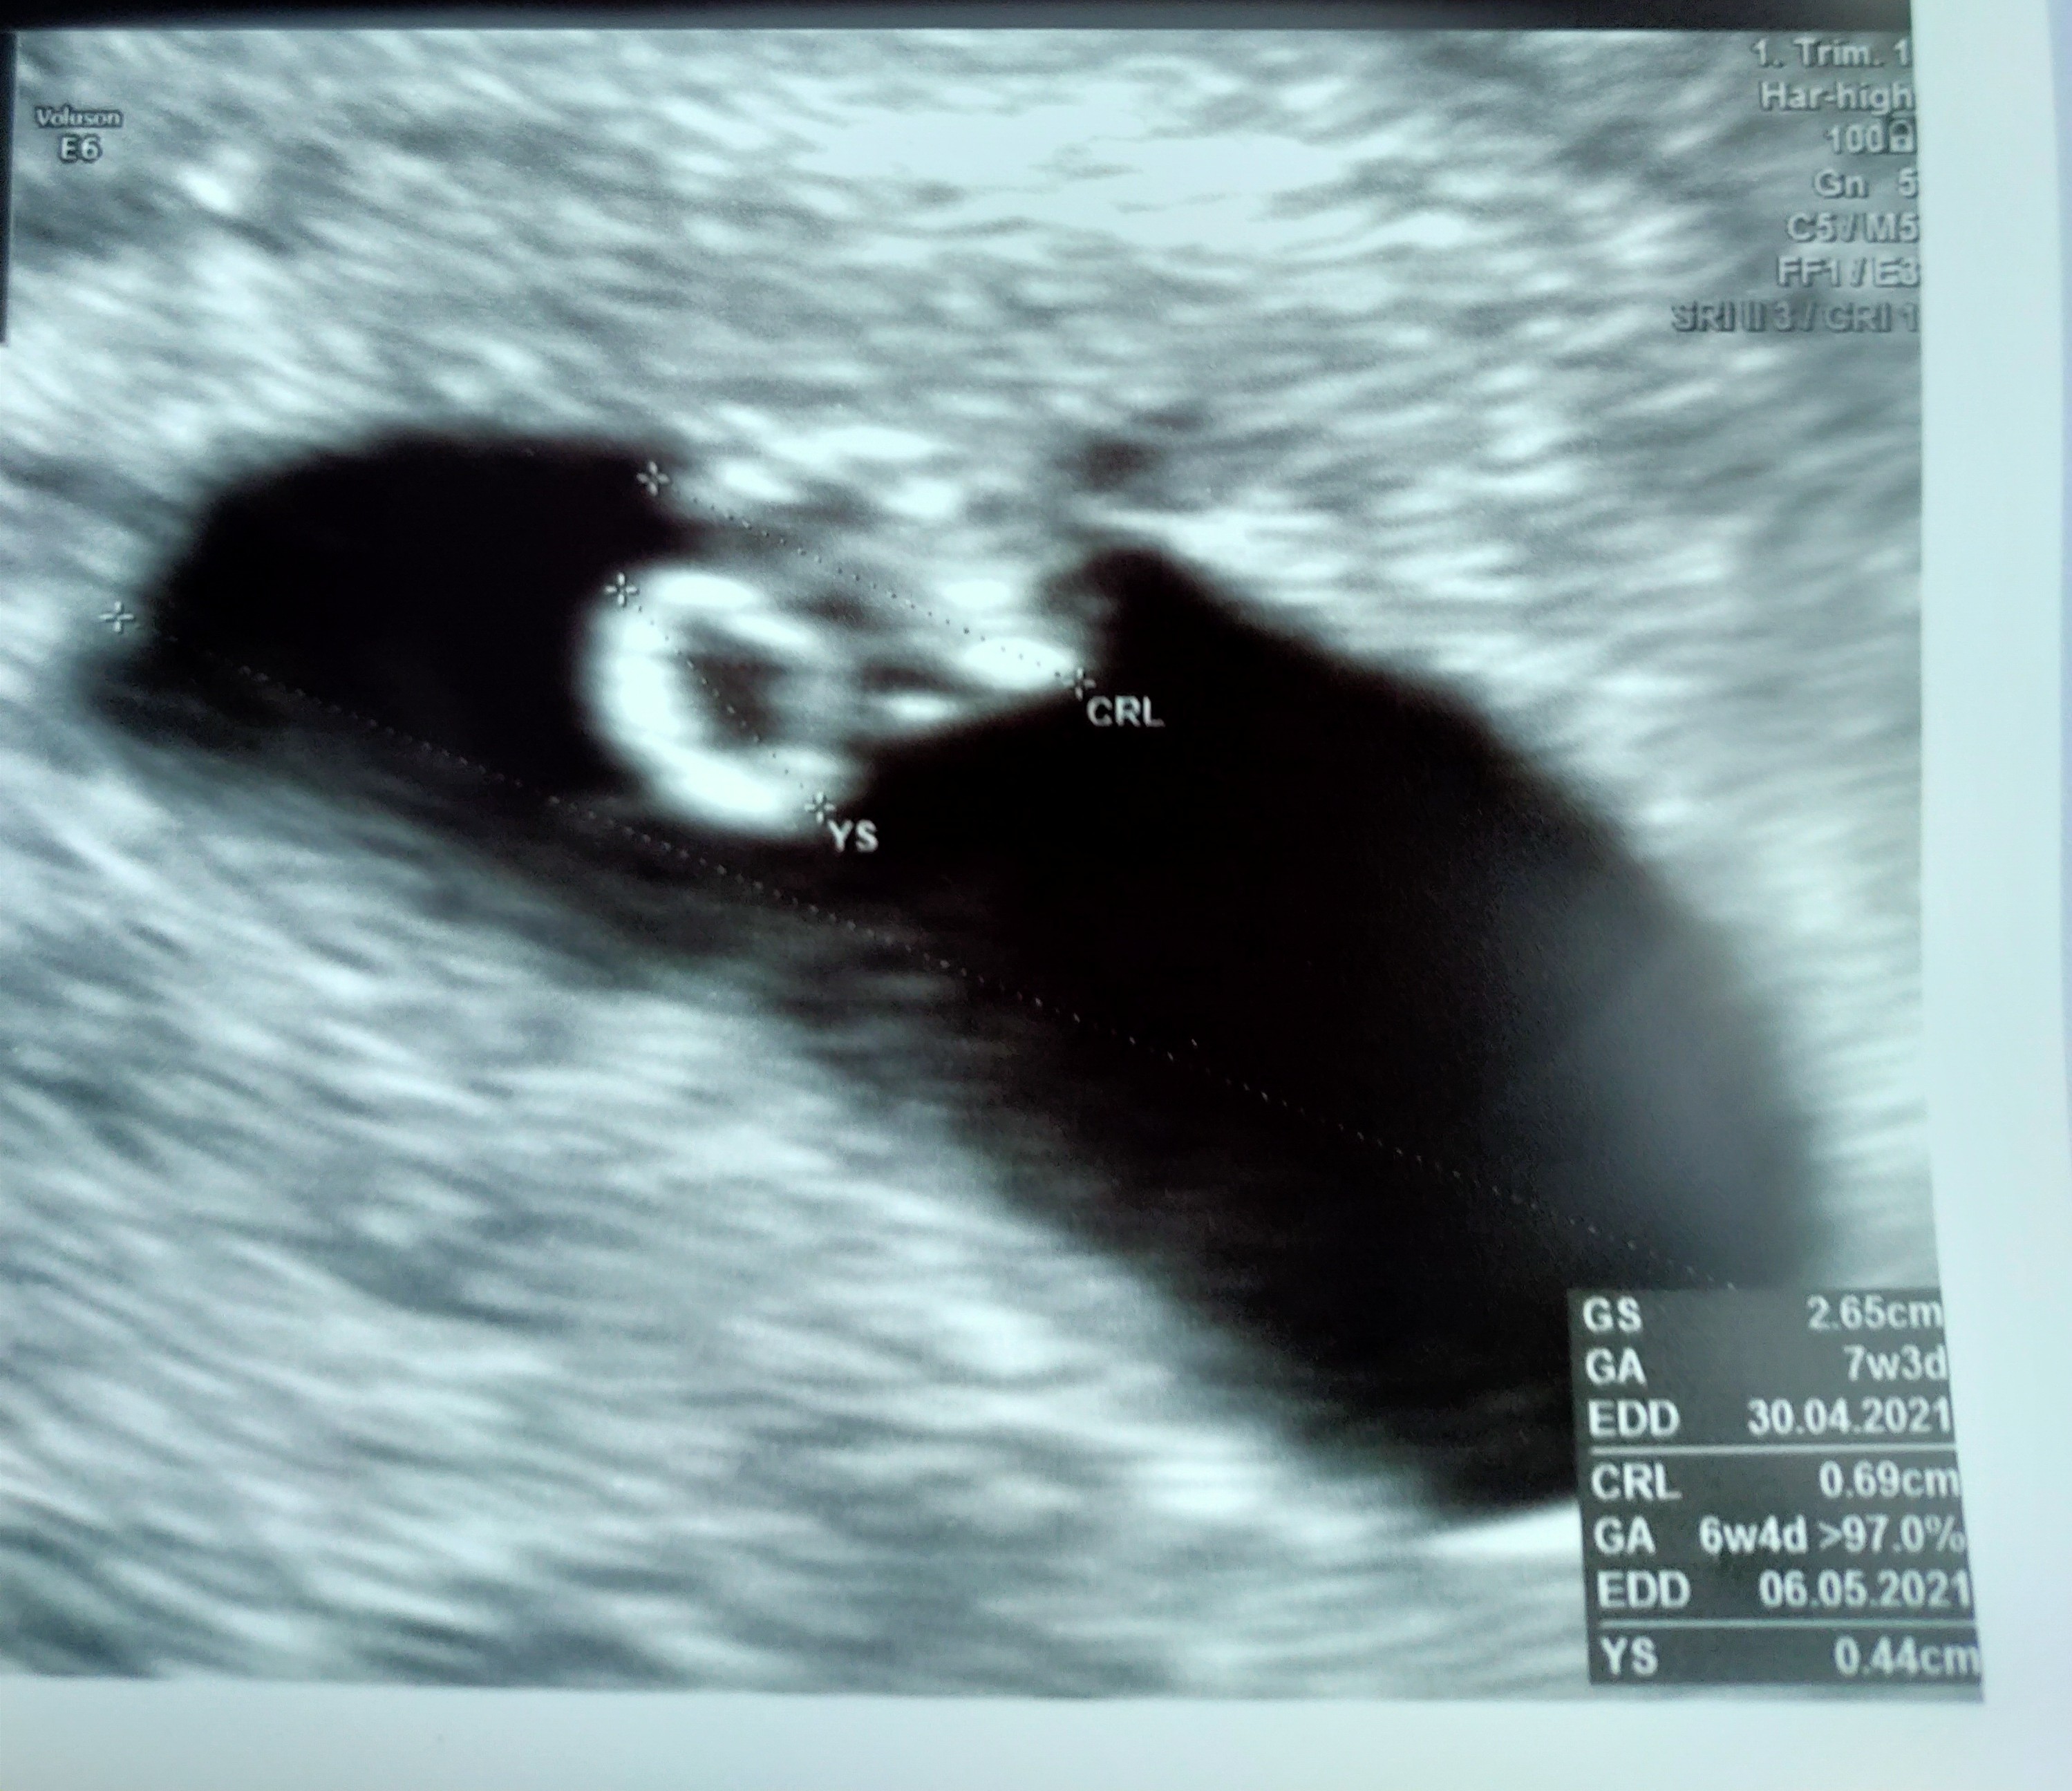

Wszystko super. Kamień spadł mi z serca ❤️ z wyliczeń lekarza 5+5 ale z USG 6+4, więc wszytsko rozwija się prawidłowo. Maleństwo ma 9mm. Serduszka nie słuchaliśmy żeby nie zaszkodzić. Kolejna wizyta za 2 tyg. Tak się cieszę ❤️❤️

Ze względu na mdłości i że w pierwszej ciąży poroniłam dostałam duphaston i zalecenie przejścia w pracy na home office a nawet propozycję od razu L4 ale muszę porozmawiać z kierownikiem.

Piękny widoczek 🥰🥰🥰